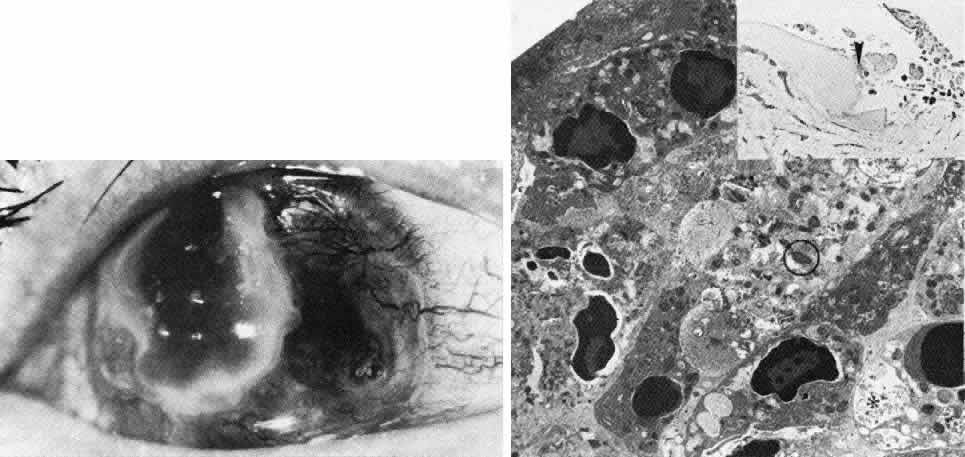

Macular Dystrophy (Groenouw Type II)

Among the classic corneal dystrophies, macular dystrophy, unlike granular and lattice dystrophies, is an autosomal recessive disorder and is far less common. It usually begins in the first decade of life and leads to progressive visual deterioration as the stroma becomes generally cloudy, with superimposed dense, gray-white spots (Figs. 5 AND 11; Color Plate 1H). Unlike granular dystrophy, these macular spots have indefinite edges and the intervening stroma is not clear. Young patients exhibit axial lesions in the superficial layers of the cornea, but with time, lesions approach the periphery and extend throughout the entire stromal thickness. Corneal thinning confirmed by central pachymetry has been documented.129 Also unique is primary involvement of the endothelium as evidenced clinically by the presence of guttate changes of Descemet's membrane.

Fig. 11. Macular corneal dystrophy. Top left. Clinical appearance of cornea features diffuse haze extending to the limbus with superimposed, dense gray-white spots. Bottom left. Light photomicrograph of posterior cornea shows endothelial cells staining intensely positive for acid mucopolysaccharide. Guttate excrescences (*) of Descemet's membrane (DM) are frequent. The stroma also shows positive staining for acid mucopolysaccharide both diffusely extracellularly and intensely within keratocytes (circled) (colloidal iron × 500). Right. Transmission electron micrograph discloses typical fibrillary granular deposits within keratocytes (K), throughout the posterior layer of Descemet's membrane, and within the endothelial cells (En). The anterior banded region of Descemet's membrane (bracketed) is not affected (× 3500).

The lesions in macular corneal dystrophy stain intensely with alcian blue and colloidal iron, minimally with PAS, and not at all with Masson's trichrome. Birefringence is decreased. The lesions have been histochemically identified as an abnormal keratan sulfate-like glycosaminoglycan that accumulates extracellularly within the stroma and Descemet's membrane and intracellularly within keratocytes and endothelium.130

As would be typical of an autosomal recessively inherited condition, macular dystrophy presumably results from deficiency of a hydrolytic enzymes (sulfotransferase) and may thus be considered a localized mucopolysaccharidosis.131 The effect of altered glycosaminoglycan metabolism is evident at the cellular level; on transmission electron microscopy, keratocytes and endothelial cells exhibit distention of rough-surfaced endoplasmic reticulum cisternae. With the acridine orange technique, compensatory generalized hyperactivity of the lysosomal enzyme system has been demonstrated.132 Eventually the accumulated undigested storage products engorge the cells, and the cells ultimately degenerate or rupture. The derivation of these intracytoplasmic storage vacuoles from endoplasmic reticulum suggests that the biochemical lesion in macular dystrophy occurs at a different metabolic location than in the systemic mucopolysaccharidoses, since in the latter, storage products accumulate within lysosomelike intracytoplasmic vacuoles associated with the Golgi complex.133 Snip and associates134 were able to determine that the storage phenomenon affecting endothelium and Descemet's membrane is likely also primary, since the intracellular and extracellular lesions appear ultrastructurally comparable to those evident in the keratocytes and stroma.

Two subtypes of macular dystrophy have been immunohistochemically identified. Type I is most prevalent and is characterized by the absence of antigenic keratan sulfate in the cornea as well as in the serum; it, in fact, may represent a more widespread systemic disorder of keratan sulfate metabolism.135 In type 2, antigenic keratan sulfate is present in both cornea and serum.

The treatment for macular dystrophy is corneal transplantation. Recurrence in the graft has been reported.119,136